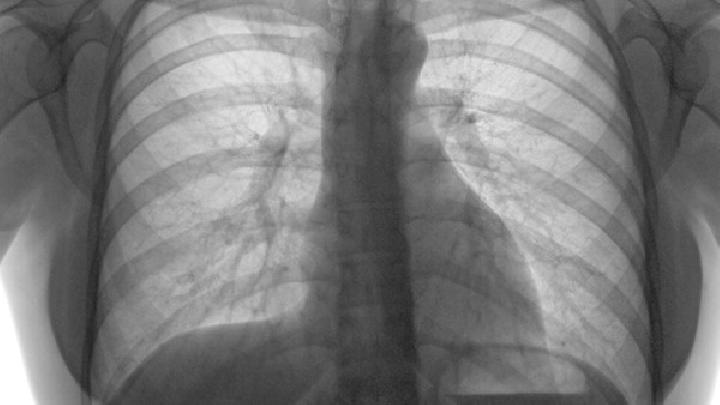

肺气肿

了解肺气肿的分类是怎样的